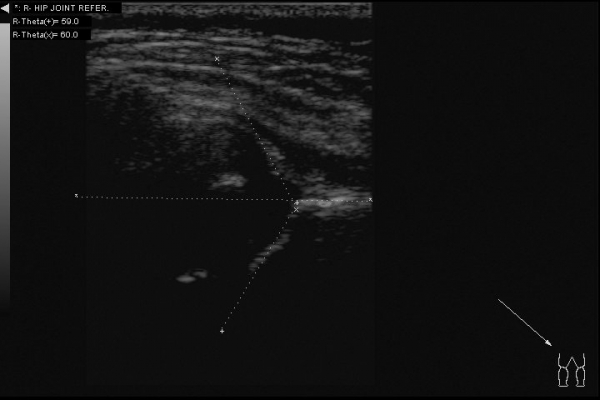

Вот еще пример, когда УЗИ картина не совсем соответствует истине:

Ребенок 6 месяцев, до обращения в наш центр неоднократно осмотрен ортопедами. Клинически -- полная норма, но насторожила какая-то чуть избыточная ротация в левом бедре. Решил выполнить УЗИ:

По УЗИ дисплазия слева, достаточно тяжелая. Может и подвывих, если придраться.

А на рентгене -- полный врожденный вывих, головка лежит вне сустава.

Тактика лечения -- другая, прогнозы - другие.